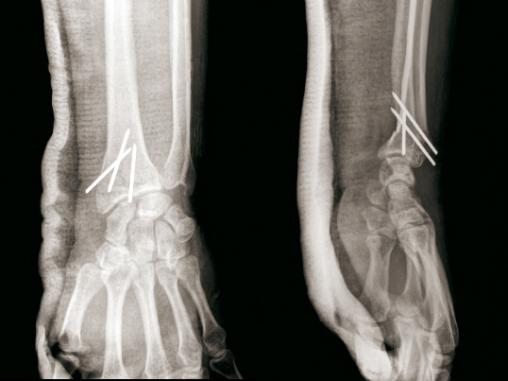

© Henry Coudane, Frédéric Éloy (La Revue du Praticien) Embrochage intrafocal selon Kapandji avec trois broches. (À gauche) Radio de face. (À droite) Radio de profil.